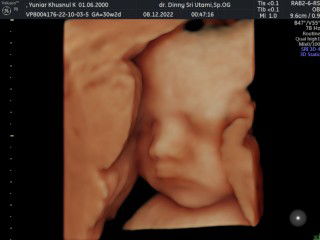

Ibu hamil